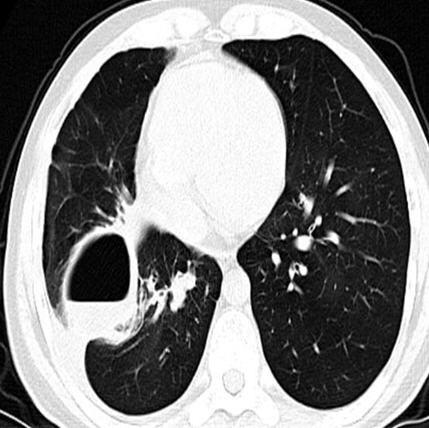

A 31-year-old asthmatic Chinese man presented with recurrent spontaneous pneumothorax and underwent lobectomy due to persistent air leakage. Aspergillus was detected histopathologically in the visceral pleural cavity. He was treated with itraconazole at 200 mg a day, and nine months later he had no recurrent pneumothorax or aspergillus infection.

一名31岁的中国哮喘男性患者出现复发性自发性气胸,因持续漏气接受了肺叶切除术。在内脏胸膜腔中通过组织病理学检测到曲霉菌。他接受了每日200毫克的伊曲康唑治疗,九个月后未再出现复发性气胸或曲霉菌感染。